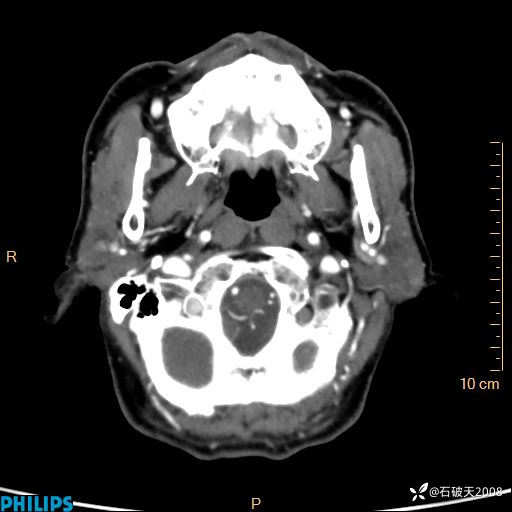

静脉期